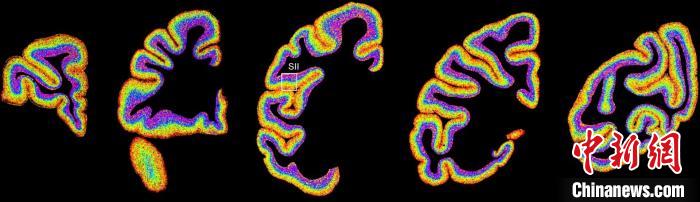

圖為(wei) 不同類型細胞在獼猴大腦上的分布切片。 中國科學院腦科學與(yu) 智能技術卓越創新中心 供圖

李澄宇說,科研人員做的事情好似“查戶口”,也就是搞明白猴腦裏有哪些細胞、這些細胞在哪些位置。搞明白這些就形成了一個(ge) 大的數據集,科研團隊挖掘這個(ge) 數據集,發現了很多有意思的現象:比如,興(xing) 奮性神經元、抑製性神經元以及非神經元在大腦皮層中的分布呈現明顯的特異性,也就是不同細胞“住”哪,有一定規律。